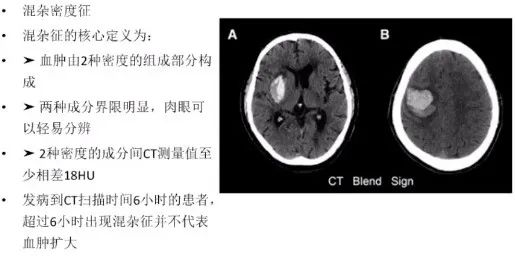

指征2:混杂密度征